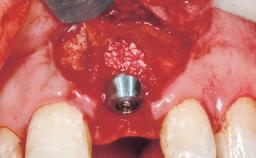

Late Flapless Placement of an Implant in a Maxillary Left Central Incisor Site

A 39-year-old male patient presented with a chief complaint of discomfort and gingival discoloration around his maxillary left central incisor. He was in good general health and was a non-smoker. His past dental history was significant because of the traumatic fracture of tooth 21 in a sporting accident at age 13. Initial dental treatment included endodontic therapy and a full-coverage restoration. The patient became symptomatic 5 years later, when structural failure of the tooth resulted in the dislodgment of the crown. Endodontic retreatment, apical surgery, and post-and-core restoration were performed.

Type of Implants One-Piece

Attachment One-Piece

Bone Augmentation Horizontal|Staged

Augmentation Materials Xenogenous|Membrane

Soft Tissue Grafting Simultaneous

Bone Volume Deficient horizontally, requiring prior grafting